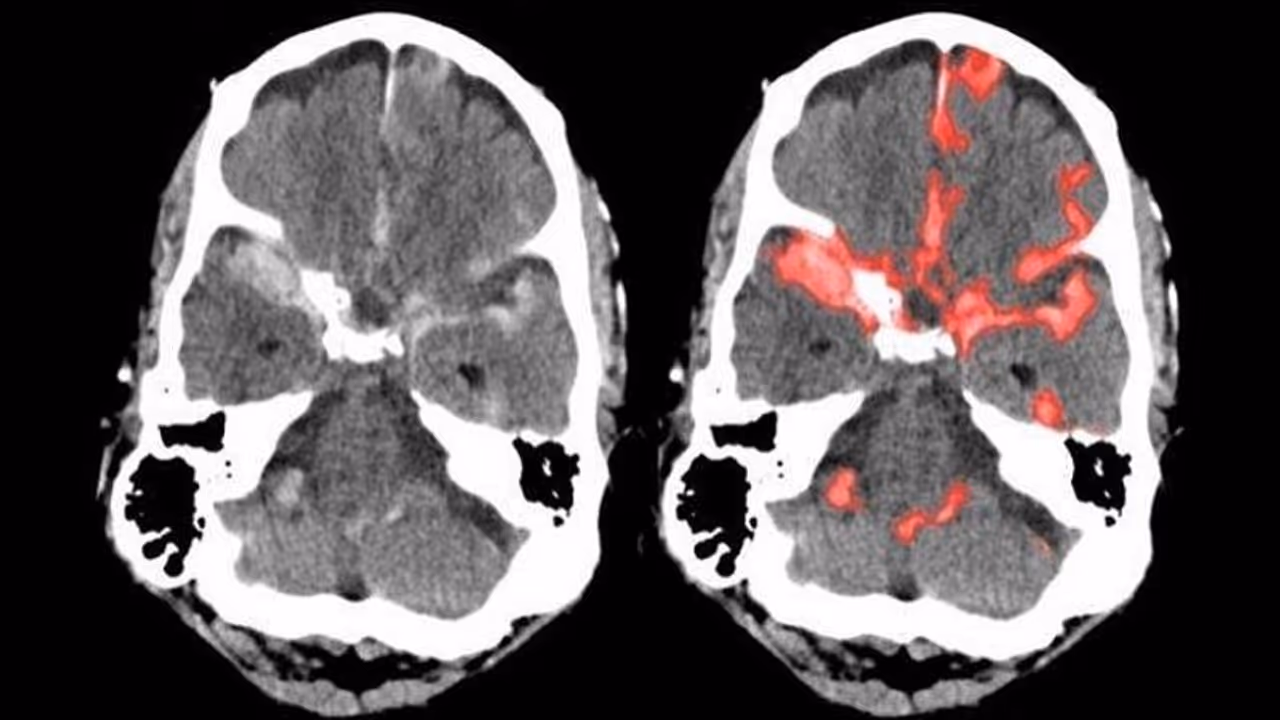

ಅದರಂತೆ ಮಾರಣಾಂತಿಕ ಬ್ರೈನ್ ಹ್ಯಾಮ್ರೇಜ್'ನ್ನು ಆರಂಭಿಕ ಹಂತದಲ್ಲೇ ಗುರುತಿಸಬಲ್ಲ ಹೊಸ ಎಐ ತಂತ್ರಜ್ಞಾನವನ್ನು ಭಾರತೀಯ ಮೂಲದ ವೈದ್ಯರು ಸಂಶೋಧಿಸಿದ್ದಾರೆ.

ಯುಸಿ ಬರ್ಕ್ಲಿ ಹಾಗೂ ಯುಸಿ ಸ್ಯಾನ್ಫ್ರಾನ್ಸಿಸ್ಕೋ ವೈದ್ಯರಾದ ಜಿತೇಂದ್ರ ಮಲಿಕ್ ಹಾಗೂ ಪ್ರತೀಕ್ ಮುಖರ್ಜಿ, ಬ್ರೈನ್ ಹ್ಯಾಮ್ರೇಜ್ ಲಕ್ಷಣಗಳನ್ನು ಗುರುತಿಸಬಲ್ಲ ಆರ್ಟಿಫಿಶಿಯಲ್ ಇಂಟೆಲಿಜೆನ್ಸ್ ಯಂತ್ರವನ್ನು ಸಂಶೋಧಿಸಿದ್ದಾರೆ.

ರೋಗಿಯ ಮೆದುಳಿನಲ್ಲಿ ಜರಗುವ ಅಸಹಜ ಪ್ರಕ್ರಿಯೆಗಳನ್ನು ಪಿಕ್ಸೆಲ್ಗಳಲ್ಲಿ ಸೆರೆ ಹಿಡಿದು ನಂತರ ಅದನ್ನು ಕೇವಲ ಸೆಕೆಂಡ್ನಲ್ಲಿ ಸ್ಕ್ಯಾನ್ ಮಾಡಬಲ್ಲ ಸಾಮರ್ಥ್ಯ ಈ ಎಐ ಯಂತ್ರಕ್ಕಿದೆ ಎಂದು ಈ ವೈದ್ಯರು ಮಾಹಿರತಿ ನೀಡಿದ್ದಾರೆ.